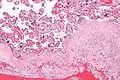

-

Acute choriodeciduitis, with neutrophils seen in the chorion and decidua.